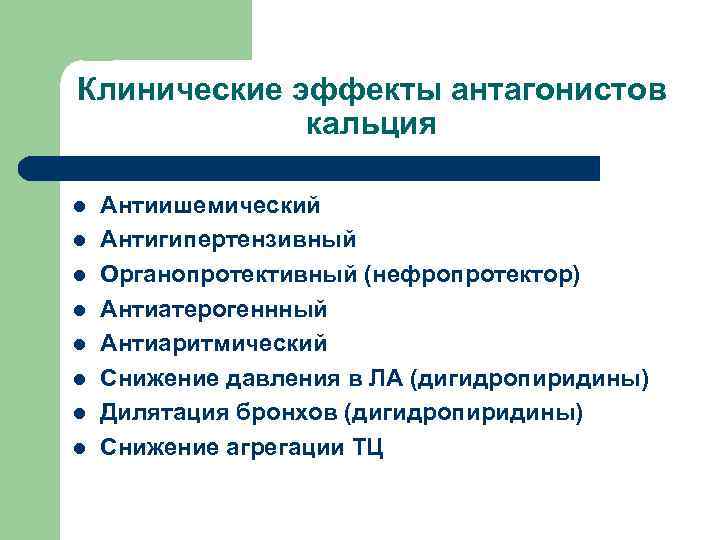

Клинические эффекты антагонистов кальция l l l l Антиишемический Антигипертензивный Органопротективный (нефропротектор) Антиатерогеннный Антиаритмический Снижение давления в ЛА (дигидропиридины) Дилятация бронхов (дигидропиридины) Снижение агрегации ТЦ